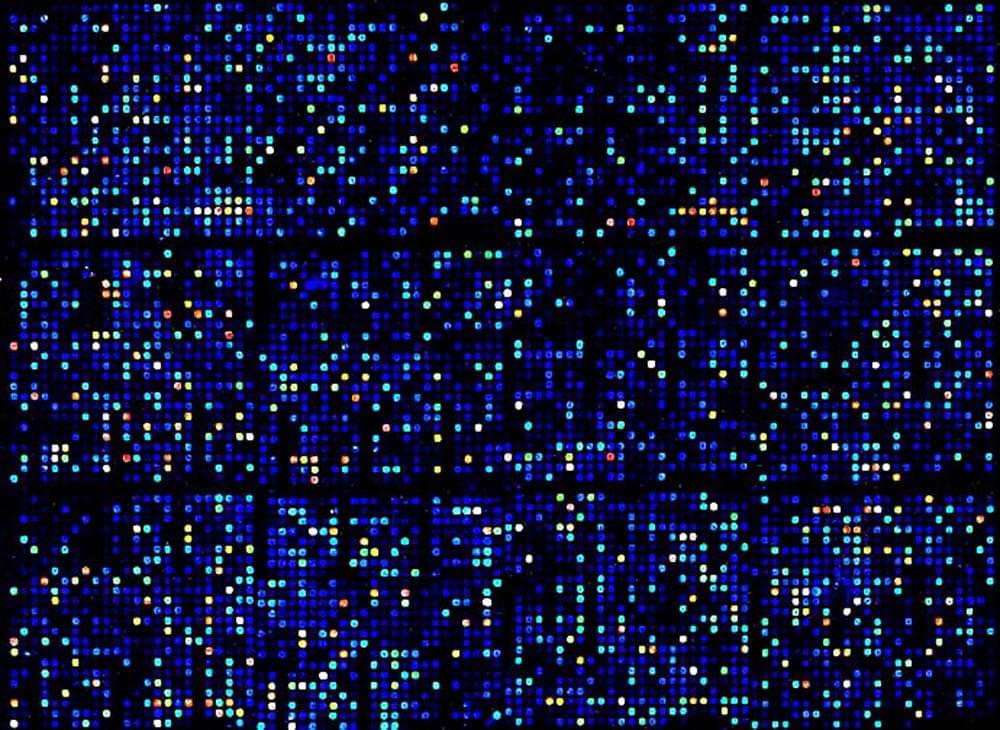

Big data is a term for data sets that are so large or complex that traditional data processing applications are inadequate. We use deep learning to analyze multi-modal Big Data such as genomics or clinical imaging from patients to reveal patterns, trends, and associations with disease. We strive to ultimately translate Big Data from the clinics into useful medical intelligence to impact clinical decisions.

We mine open data to understand defective patterns of genomics disease signatures. We integrate genomic signatures of drug response to select optimal agents that directly reverse disease genomics. Our goal is to develop more personalized therapeutic options to fight disease.

is an open genomics discovery web platform to annotate digital samples housed within NCBI Gene Expression Omnibus (GEO) and to find robust genomic signatures of disease. We enlist the help of medical students without coding experience to generate genomic signatures of disease which we integrate with other large databases to discover novel biomarkers to diagnose or more optimal therapeutic interventions to treat disease. STARGEO is an NCI funded project through the NIH BD2K NIH initiative to characterize the functional genomics of disease with open data.